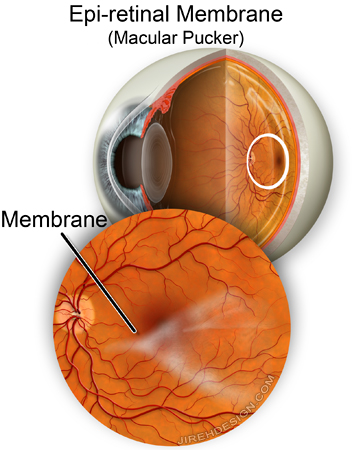

Görme merkezi önünde zar oluşumu:

(Makula zarı, Maküler Epiretinal Membran, Macular pucker)

Makula önü zarı, detay görmeyi sağlayan, görme merkezi (makula) önünde ince bir zar tabakasının oluşmasıdır.

Çoğu zaman makuladaki retina önündeki zarlar çok ince olduğundan hiçbir belirti vermeden yıllarca sessiz kalabilirler. Zamanla zarda gelişen kalınlaşma görme merkezinde çekintiye yol açarak görmede bulanıklaşmaya, cisimlerin eğri görülmesine neden olurlar.

Bazen makula önü zarı zamanla kalınlaşır, retinaya çekinti uygular ve görme kalitesini bozar, bulanık ve eğri görme gibi şikayetlere neden olur. Makula önü zarı tedavisinde amaç bu zarı olduğu yerden kaldırmakır. Makula önü zarı tedavisinde kullandığımız vitrektomi cihazlarındaki gelişmeler uyguladığımız teknikde devrim sayılabilecek değişikliklere imkan yartamıştır. Kullandığımız enstrumanlar o kadar incelmiştir ki ameliyat bitimde dikiş kullanma ihtiyacı önemli ölçüde ortadan kalkmıştır. Bu durum ameliyat süresinin kısalmasına, yara iyleşmesinin hızlanmasına imkan yaratmaktadır.